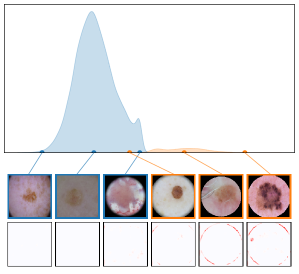

We further plot the distribution of CAV-based bias scores for biased and clean samples for the real-world artifacts ruler (ISIC2019) and pacemaker (CheXpert) in Fig. 8. We compute bias scores using the best performing CAV per artifact and use latent activations after the residual block of the ResNet50 model for ruler, and the convolutional layer of the VGG16 model for pacemaker. We show samples corresponding to the bias score in the top-1 and -99 percentiles of each set. Samples near the decision boundary are particularly interesting, as they may arise from labeling errors. Both examples demonstrate the retrieval of unlabeled artifact samples. The distributions of bias scores for additional artifacts are shown in Appendix A.6.2.